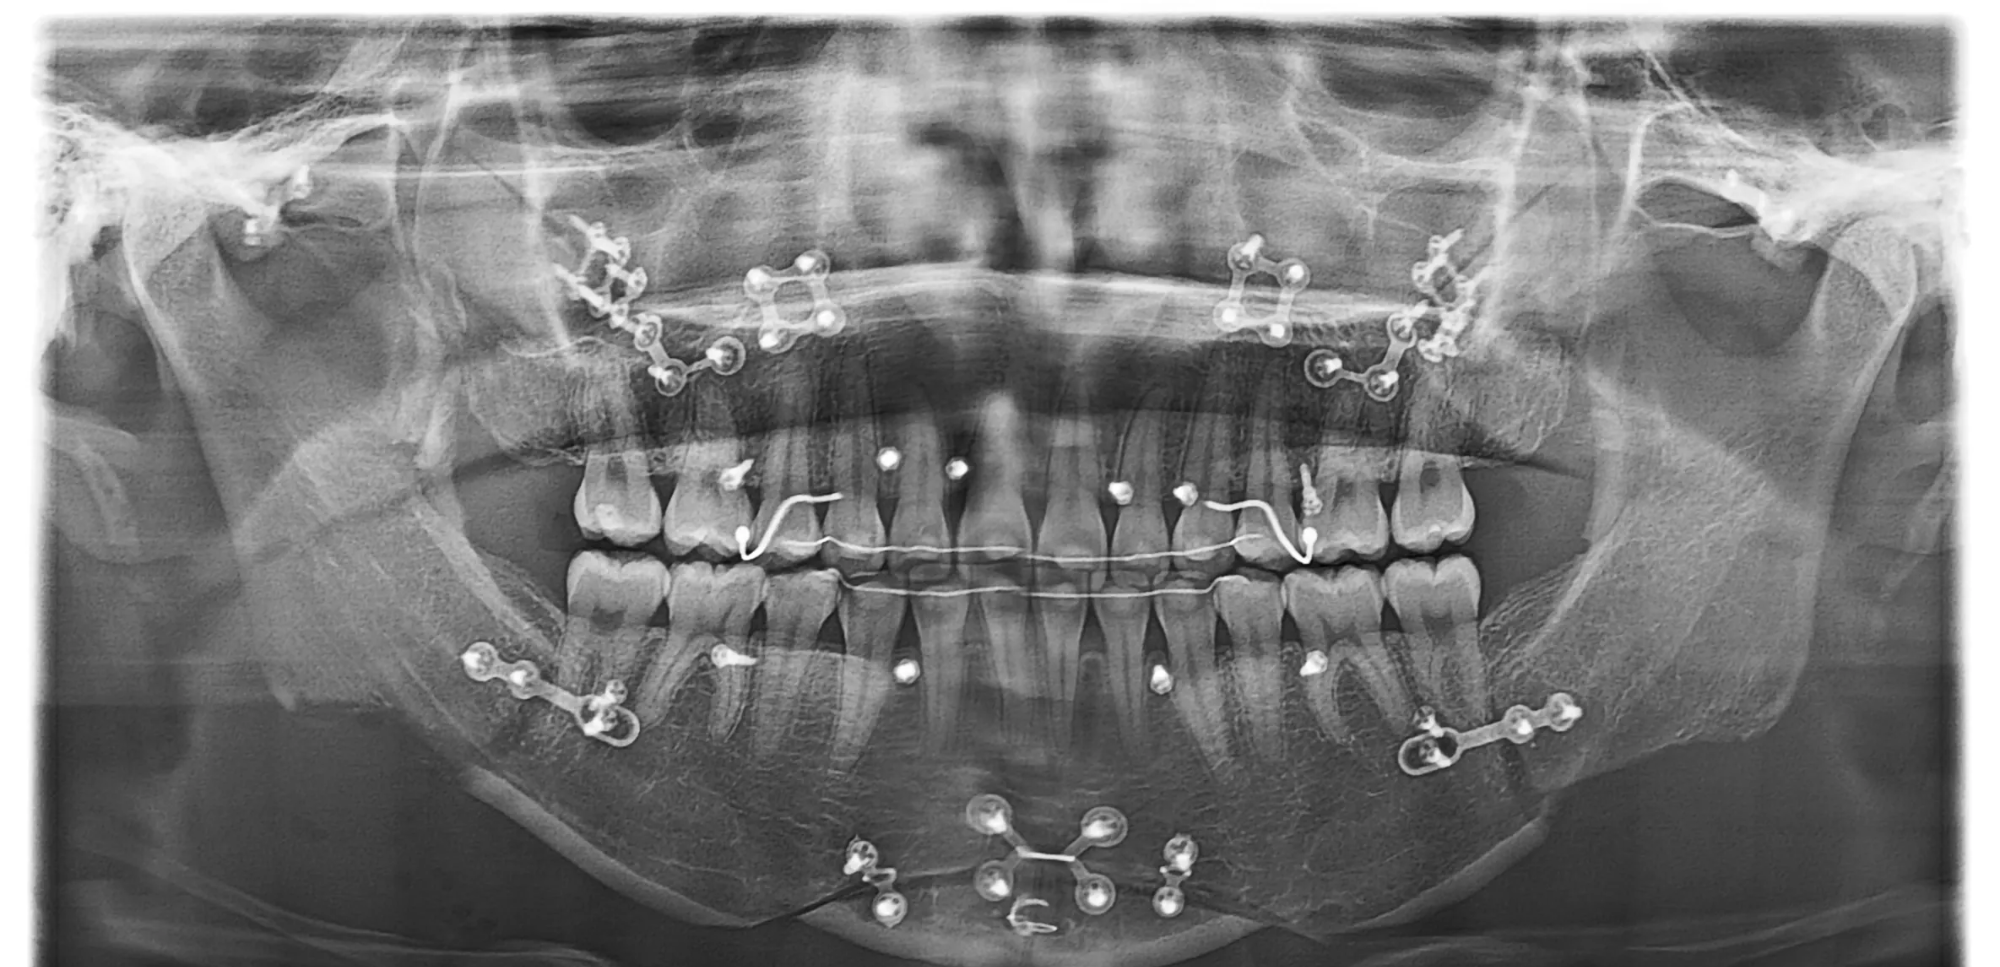

수술 전 3D CT로 핀 위치,

골유합 상태, 주변 신경/혈관

위치를 정확히 분석

3D 시뮬레이션과 수술 계획 수립

3D CT 촬영 및 시뮬레이션, 원장님 정밀 상담 후

환자 맞춤형 수술 방향 결정